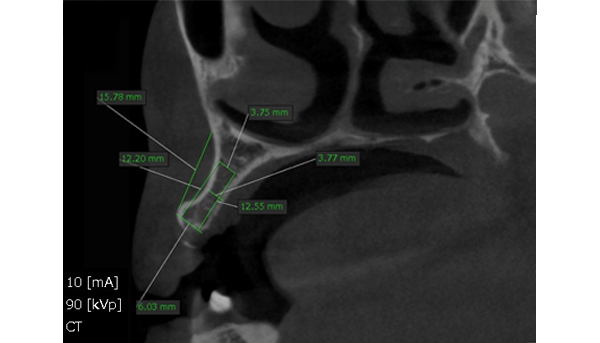

CT画像

「3.7mmという限られた骨幅に、

インプラントを精密に埋め込む技術」

通常、骨の厚みが十分でない場合は治療が難しくなります。

しかし当院では、3.7mm以下という極めて限られた骨幅にも対応できる精密な埋入技術を持っています。

ミクロン単位での位置決めを可能にする専用の診断・手術機器と、豊富な経験を積んだ歯科医師の技術力があってこそ実現できる治療です。

その結果、骨の状態に制約があっても、安全性と長期安定性を両立したインプラント治療をご提供できます。